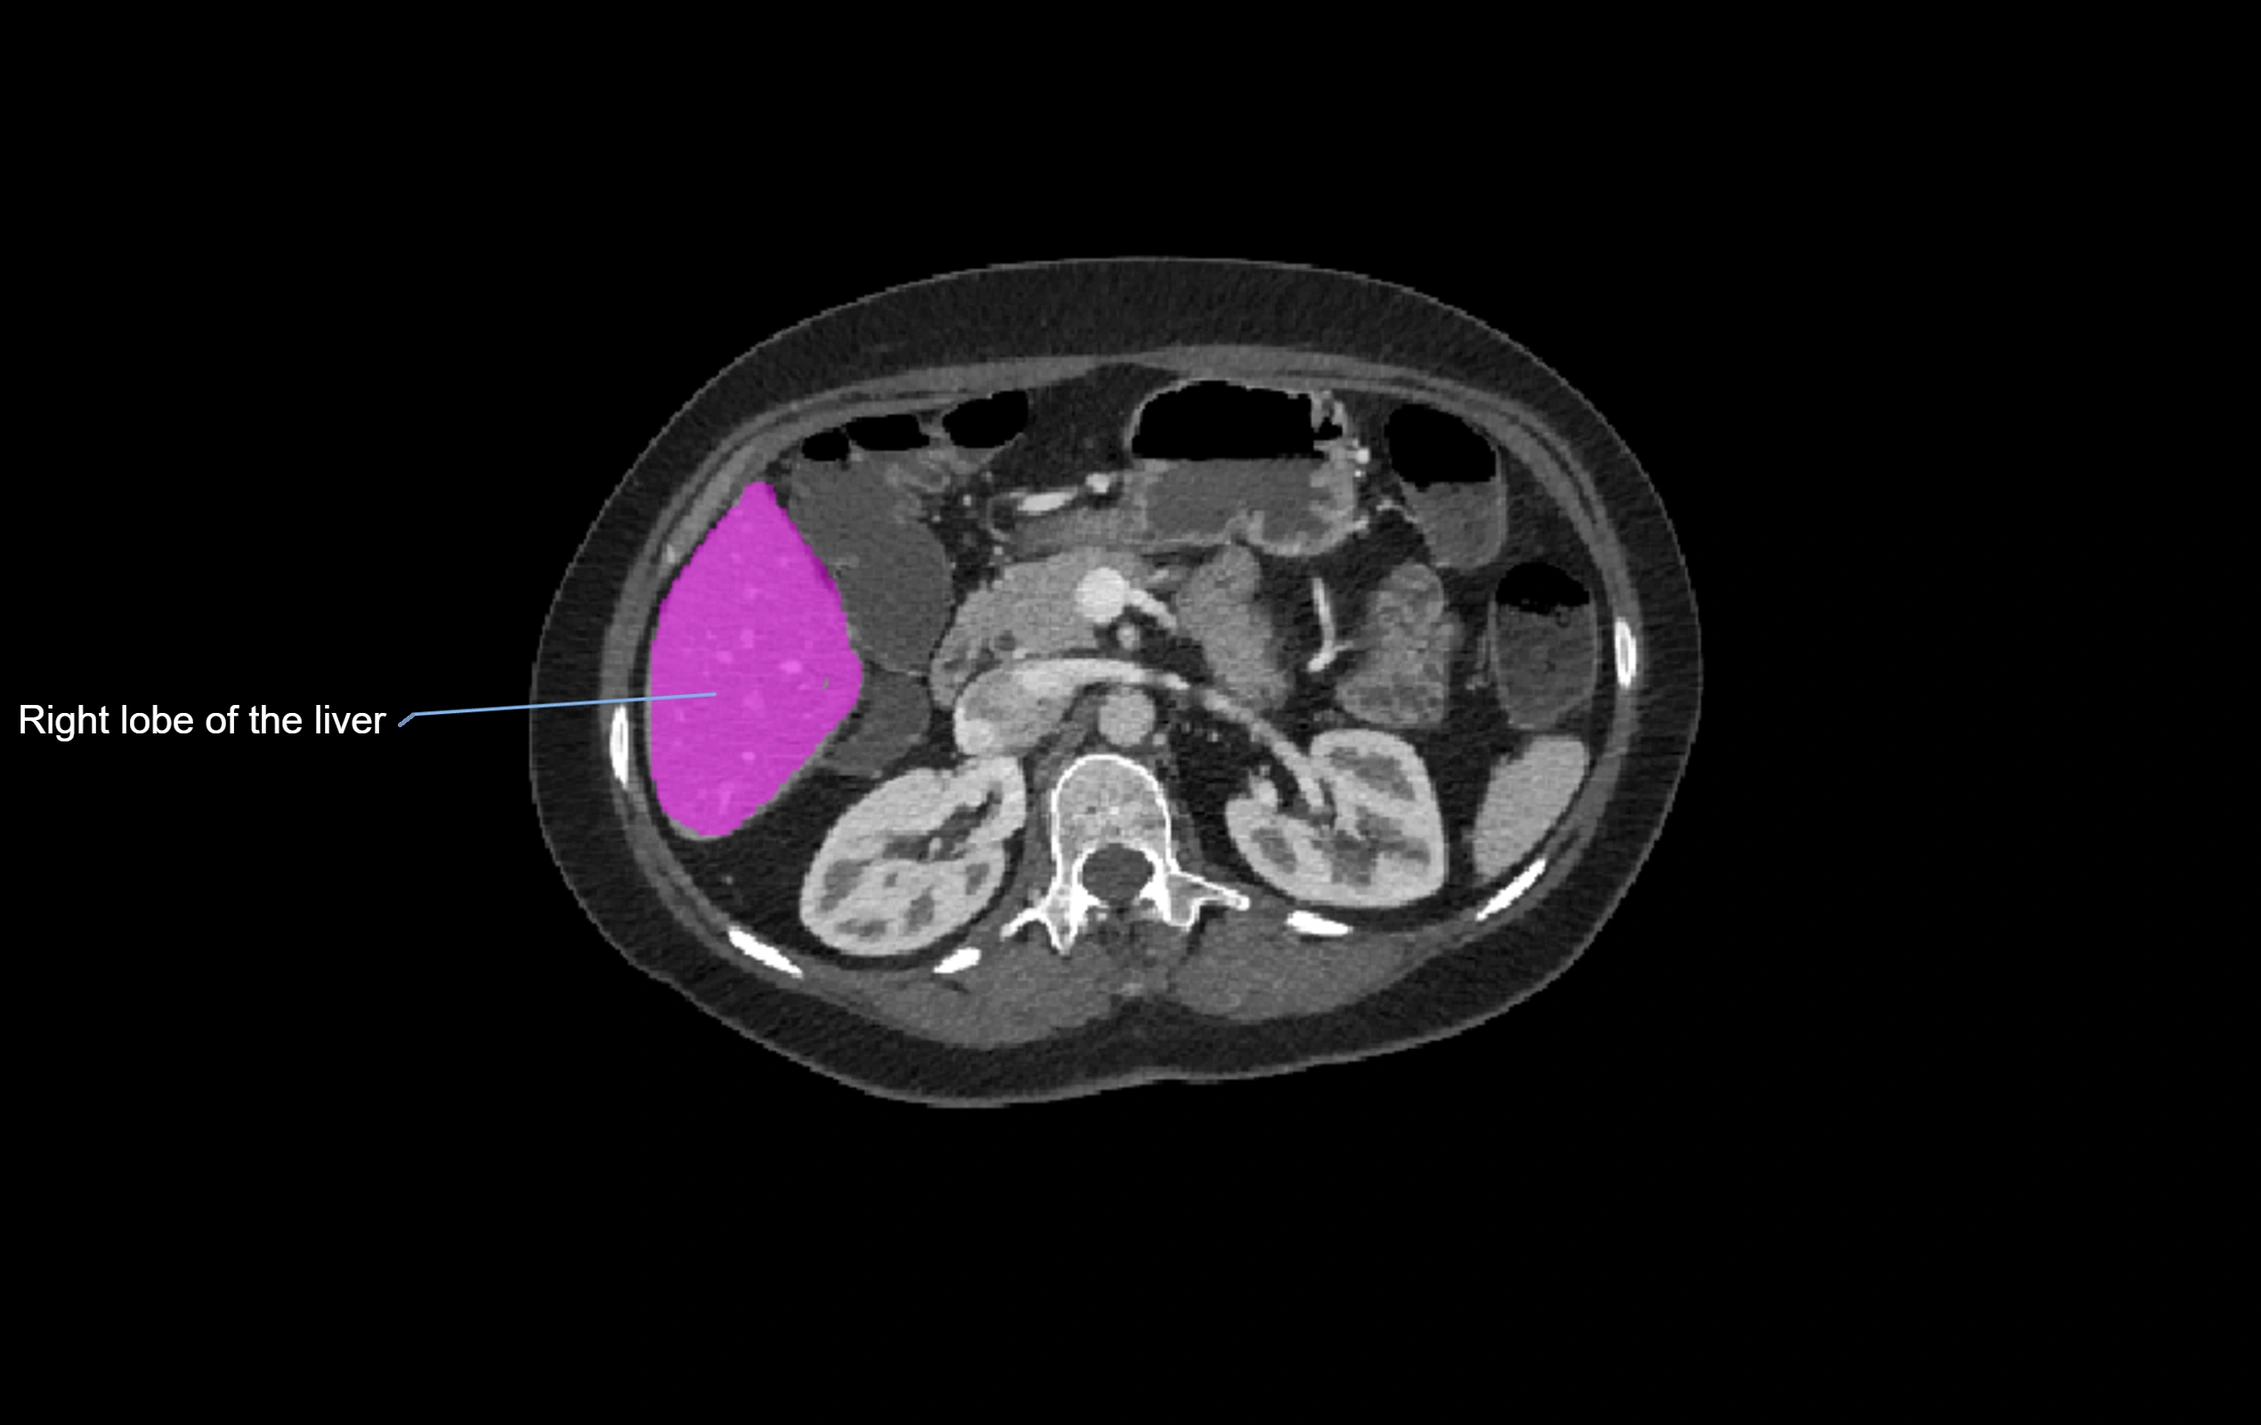

CT Image

image